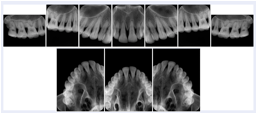

OO.1.2 Ophthalmology

1. A patient in rural Canada visits a general ophthalmologist and is found to have diabetic macular edema. The general ophthalmologist would like to discuss the case with a retina specialist before performing laser surgery. A fluorescein angiogram is done with multiple retinal images taken in a timed series after an intravenous injection. The images along with a Structured Display are shared via a Health Information Exchange with a retina specialist in Calgary, who opens them using his Ophthalmology EMR software and consults via phone with the general ophthalmologist. Both physicians view the images in the same layout so the retina specialist can provide accurate guidance for treating the patient.

2. A patient in rural Iowa visits his primary care physician for management of diabetes. Three non-mydriatic (patient's eyes are not dilated) photographs are taken of the back of each eye, and forwarded electronically along with a Structured Display to an ophthalmologist in Iowa City. The ophthalmologist reads the photos in an agreed upon layout so there is no mistake about what portion of which eye is being viewed. The ophthalmologist is able to tell the primary care physician that his patient does not need to come to Iowa City for face to face ophthalmologic care, but that there is a particular view of the left eye that should be photographed again in 6 months.

Ophthalmic Retinal Study Structured Display

Figure OO-3. Ophthalmic Retinal Study Structured Display